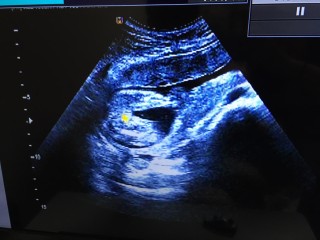

写真:21w4d:ちゃまたろーさん:一卵性双子

一卵性の双子です。初めてツーショットが撮れました。380gと400gです。身長は2人とも25cm。順調です!